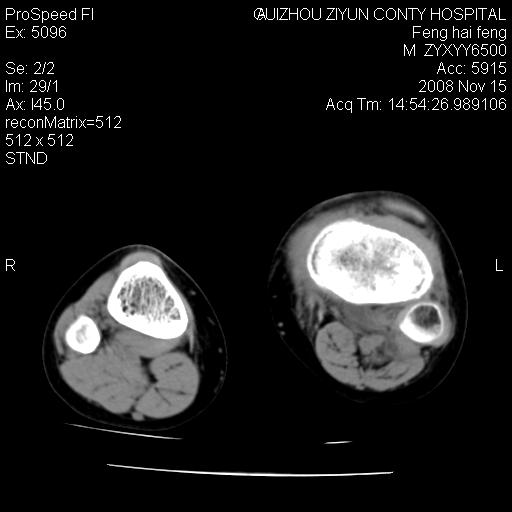

标题: CT16656:M 14Y 左膝关节肿胀一年余。其余病史不详。 [打印本页]

标题: CT16656:M 14Y 左膝关节肿胀一年余。其余病史不详。

考虑左侧髌骨结核;左膝关节滑膜肿胀、增厚,关节囊积液。

左膝滑膜型关节结核可能性大!支持!滑膜型关节结核主要ct表现:关节囊肿胀,积液,关节面见小破坏灶,并见点状死骨!

左膝滑膜型关节结核可能性大!支持!滑膜型关节结核主要ct表现:关节囊肿胀,积液,关节面见小破坏灶,并见点状死骨

好大的左腿!考虑左侧髌骨结核,左膝关节滑膜肿胀、增厚,关节囊积液。

左侧髌骨结核;左膝关节滑膜肿胀、增厚,关节囊积液